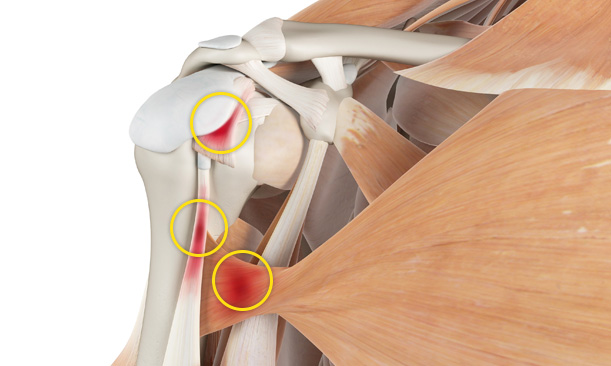

어깨충돌증후군이 발생하게 되면 회전근개에 염증이 발생하게 되고

급성 부종을 일으키게 됩니다.

30대를 시작으로 50대까지 증상이 지속적으로 악화되고 통증도 점차 커집니다.

증상이 심한 경우 일상 생활에 어려움이 발생되어 수술적인 치료를 고려할 수 있습니다.

팔을 올릴 때 어깨 앞쪽, 옆쪽에서

통증이 느껴집니다.

어깨에서

소리가 발생합니다.

어깨가 아픈 쪽으로

눕지 못하는 경우가 발생합니다.